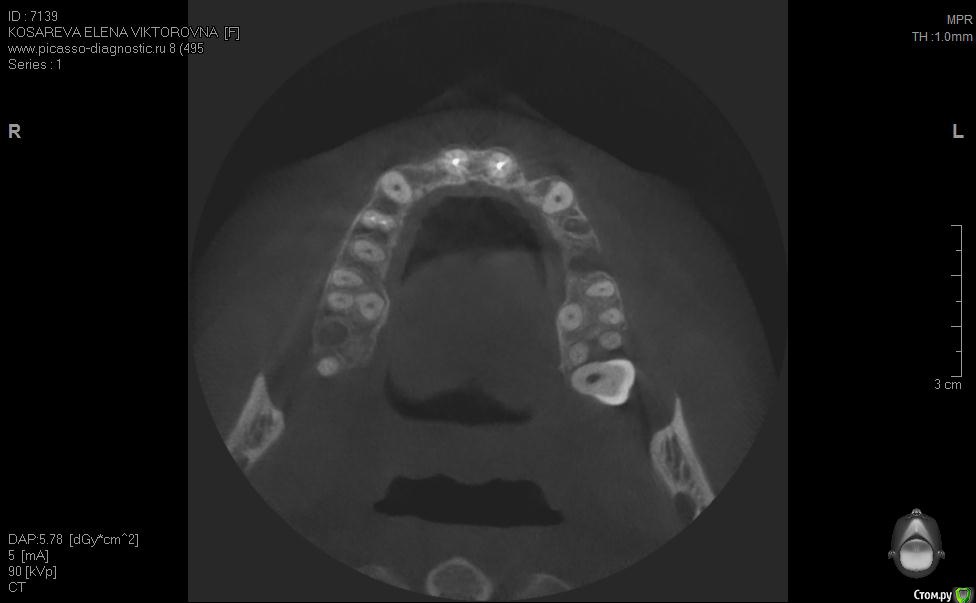

Уважаемые коллеги помогите пож с планом лечения, хотелось бы услышать ваши планы лечения,

пациент хочет красивую улыбку и импланты, клыки трогать категорически отказалась как опоры под временные на период интеграции имплантов